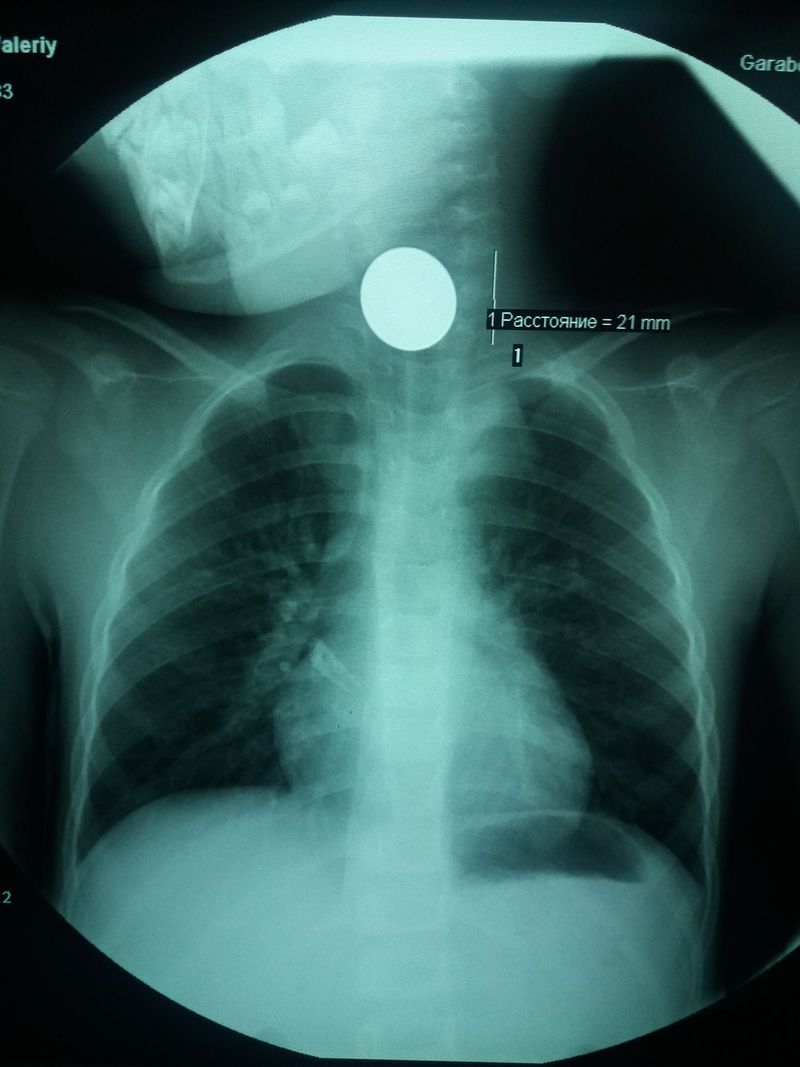

Foreign body

Most probably a Coin

Also need a lateral view to confirm the coin is not outside the body😊😊

A wafer? Or Silver Dollar coin